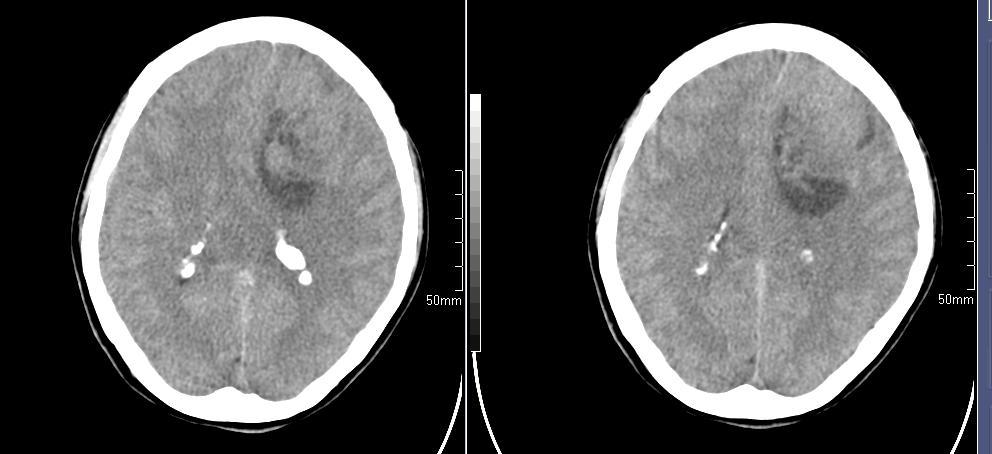

标题: CT23966:女,34岁,近一月头痛、意识障碍 [打印本页]

标题: CT23966:女,34岁,近一月头痛、意识障碍

左侧额叶见不规则软组织影,部分囊变,病变略呈等密度,占位效应明显,考虑血母可能。脑膜瘤不除外

左侧额叶肿瘤样病变,成等密度,其内可见囊变,肿瘤似与大脑镰相连,周围水肿不明显。考虑脑膜瘤可能!建议强化或mri。

左额叶囊实性肿块,实性部分呈等密度,密度不均,考虑胶质瘤可能性大,脑膜瘤及室管膜瘤不除外,建议mri增强扫描。

左额叶低分化星形细胞瘤或胶质母可能性大。建议增强。

左额叶较大等低混杂密度影,占位效应明显,首先考虑:左额叶胶质瘤。